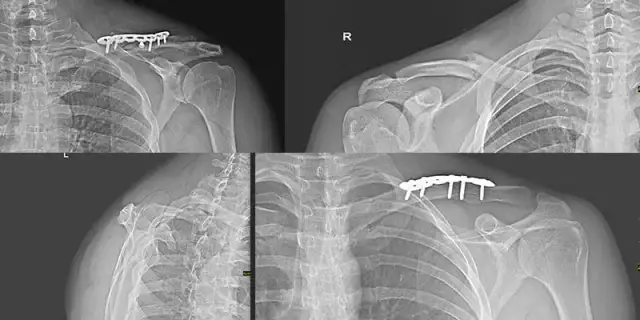

Ile trwa rehabilitacja po złamaniu obojczyka i co warto wiedzieć?

Ile trwa rehabilitacja po złamaniu obojczyka? Sprawdź, jakie czynniki wpływają na czas powrotu do zdrowia i jak skutecznie zarządzać bólem.